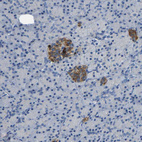

Immunohistochemistry analysis in human rectum and liver tissues using HPA012943 antibody. Corresponding C15orf48 RNA-seq data are presented for the same tissues.